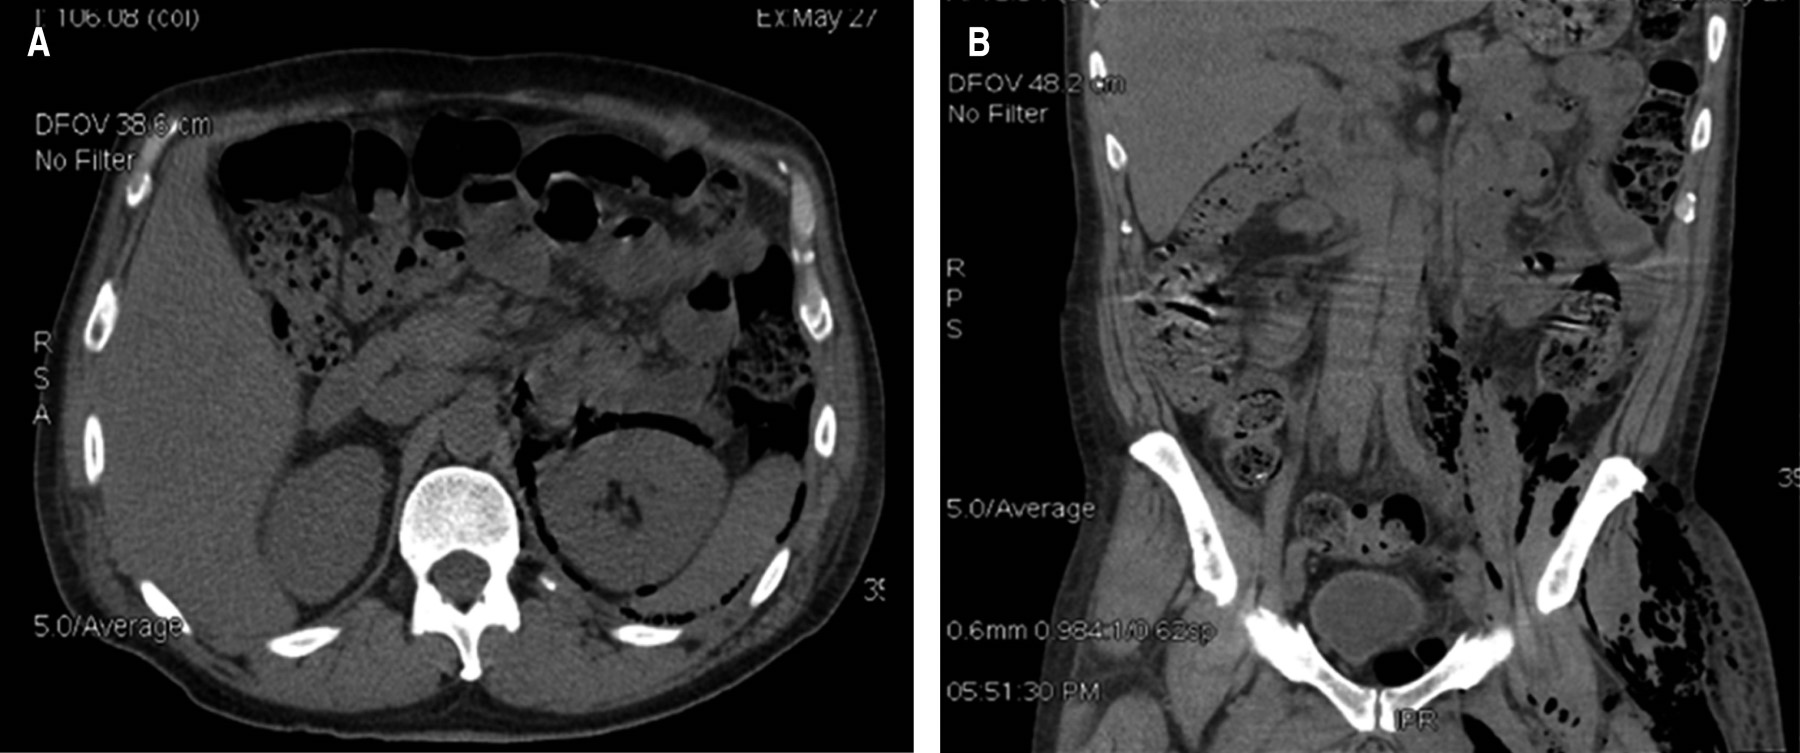

La tomografía mostró un absceso retroperitoneal en el lado izquierdo que diseca hasta la región glútea y muslo ipsilateral, así como un engrosamiento de la pared del recto, también se evidenció la presencia de lesiones hipodensas en el parénquima hepático compatibles con metástasis tumorales (Figuras 1 y 2).

La tomografía axial computarizada (TAC) es el estudio de elección en el diagnóstico y etapificación de esta complicación infecciosa-neoplásica, con una sensibilidad del 95%, aunque a veces no es posible identificarla hasta la intervención quirúrgica.13 La TAC puede mostrar neumatosis colónica hasta en el 16% de los pacientes, y puede ser un signo de inminente perforación.5 Se pueden observar colecciones con densidad de líquido, aire libre retroperitoneal, cambios en la grasa pericólica y engrosamiento de la pared colónica, sin embargo, estos cambios también pueden producir enfermedades benignas, por lo que el diagnóstico prequirúrgico es difícil.5

Figura 2